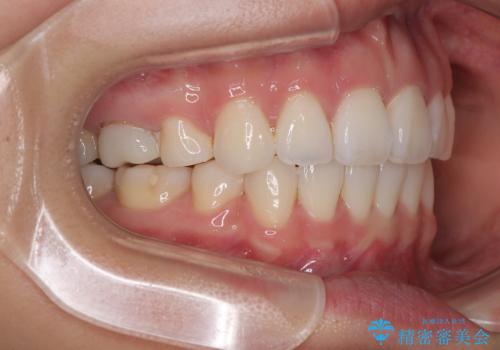

- 前歯が突出して、眠るときに口が開いてしまうことを気にして来院された患者様です。

横から見た際の口元の飛び出した印象も改善したいとのことで、上下左右の第一小臼歯4本を抜歯し、ワイヤー装置にて抜歯矯正を行うこととしました。